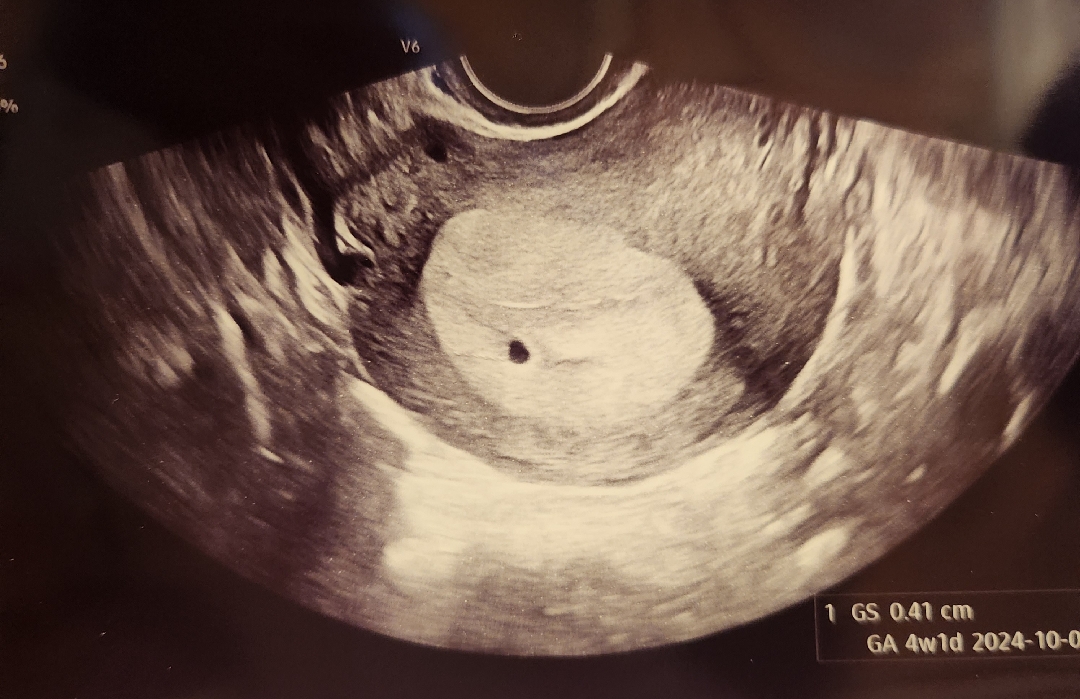

첫초음파 보고왔어요!!! 너무작나용?

5주생각했는데 4주1일이라고 하더라구여ㅜㅜ 그래도 아기집보니까 너무 벅차여 임테기로만 확인하다가 아진짜있긴있구나 싶고... 다음주엔 더 커져있겠져?